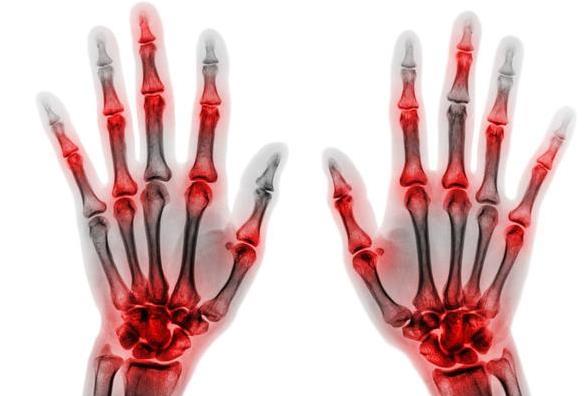

手の指 骨折 全治何週間? 症状や部位によって違いますが、通常2~4週間の固定期間が必要とされていますので、もし2週間で骨がついている状態であれば、リハビリをして間に合うと思いますが、こ 突き指と骨折はどう見分ける? 突き指は時間が経つと痛みが引いていきますが、骨折の場合は、痛みが徐々に強くなるという特徴があります。 通常、骨折を起こすと、突き指や打撲より重く症状があらわれます。 特に、ケガをした直後5~15分以内に 中手骨骨折 は、手の骨折の一種です。 中手骨と呼ばれる、手のひらや手の甲の部分の骨が骨折したものを言います。 素手で固いものを殴ったり、手の上に重い物が落ちてきたりと

骨折を放置すると、腫れや痛み、内出血などの症状がさらに悪化する恐れがあります。 また、変形した状態で骨折が治癒してしまうと、 指が曲がったまま戻らない 指を動かしにくくな手の骨折 -原因、症状、診断、および治療については、msdマニュアル-家庭版のこちらをご覧ください。 や、ゴルフのプレー中にクラブで芝生を打ったときなどに起こります。手のひらの下部